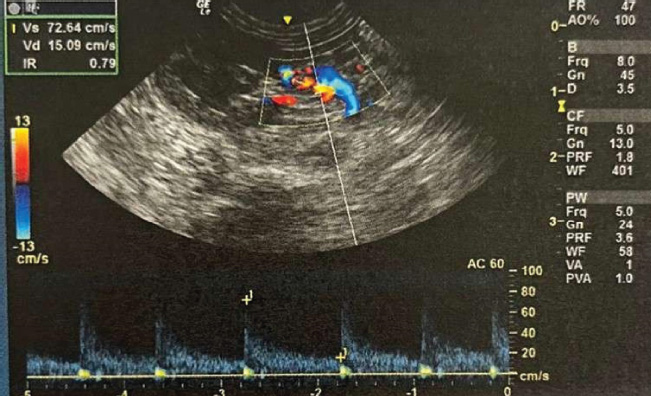

The Doppler mode has different techniques: Spectral Doppler: displays a graph of the flow over time; Color Doppler: maps the flow with colors, red for flows toward the transducer and blue for opposite flows (Carvalho et al., 2008a); Continuous Doppler: detects high flow frequencies, but without exact location of the depth; Amplitude Doppler: more sensitive to weak flows, but without indication of flow direction (Carvalho et al., 2008b).

Color Doppler

Color Doppler overlays the B-mode image with color-coded frequency shift mapping. Flows toward the transducer appear in red and opposing flows in blue. The intensity of the colors varies with the flow speed (Thomas et al., 1993; Szatmári, et al., 2001). This technique can quickly assess the presence, direction, and quality of flow in large areas, even when B-mode detection does not identify vessels (Carvalho et al., 2008a).

The IR is calculated as (PSV—EnDV)/PSV, reaching a maximum value of 1 when EnDV is zero. It is an indirect marker of vascular resistance but can show normal values even when systolic and diastolic velocities increase simultaneously (Novellas et al., 2007; Novellas et al., 2010; Ferrandis et al., 2013; Lee, 2013). The IP calculated by (PSV—EnDV)/TAMAX complements the IR by including the average of the maximum velocity throughout the cycle and is more sensitive to differentiating abnormal waves (Ferrandis et al., 2013).

Changes in PSV, EnDV, IR, and IP indicate vascular stenosis, changes in vascular bed compliance, parenchymal dysfunctions, malignant diseases, and implant rejection (Carvalho et al., 2008a). An increase in peripheral resistance, such as in obstructions or vasoconstrictions, reduces EnDV more than PSV, resulting in high IR and IP values. These indices correlate strongly with arterial capacitance, thereby aiding hemodynamic assessment (Novellas et al., 2007; Dos Reis et al., 2014).

The best image of the celiac artery is obtained with the patient in the right dorsal or lateral decubitus position, close to the right kidney (Carvalho et al., 2008a). The transducer is positioned ventrally to the lumbar processes and tilted dorsally to locate the aorta. With the aorta in a longitudinal plane, the transducer is moved cranially until the celiac artery and the cranial mesenteric artery are identified above the origin of the renal arteries. The celiac artery has a semiparabolic flow velocity profile and an intermediate resistance pattern. A broad systolic peak is observed with a well-defined mean spectral window and absence of reverse diastolic flow (Szatmári et al., 2001; Carvalho et al., 2008a).

Cranial mesenteric artery

Located below the celiac artery and above the right renal artery, the cranial mesenteric artery forms a “V” in the sagittal plane with the celiac artery when the patient is in the supine position. In the right lateral decubitus position, both directions follow parallel paths until they approach this point (Carvalho et al., 2008a). In spectral Doppler mapping, the cranial mesenteric artery shows a flow pattern of intermediate resistance with a broad systolic peak and small spectral window. After the systolic peak, the flow velocity decreases abruptly, accelerates, and then decelerates again. During fasting, the flow is of high resistance and of low resistance in the postprandial period due to increased blood flow to the stomach, duodenum, and pancreas after food intake (Carvalho et al., 2008b).